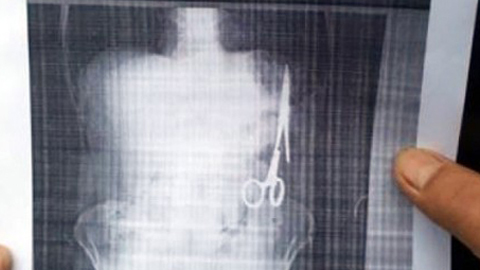

Bác sĩ bỏ quên kéo trong bụng bệnh nhân 18 năm

Sau tai nạn giao thông, ông Nhật vào bệnh viện chụp chiếu, bất ngờ phát hiện trong bụng có một chiếc kéo dài hơn 15cm.